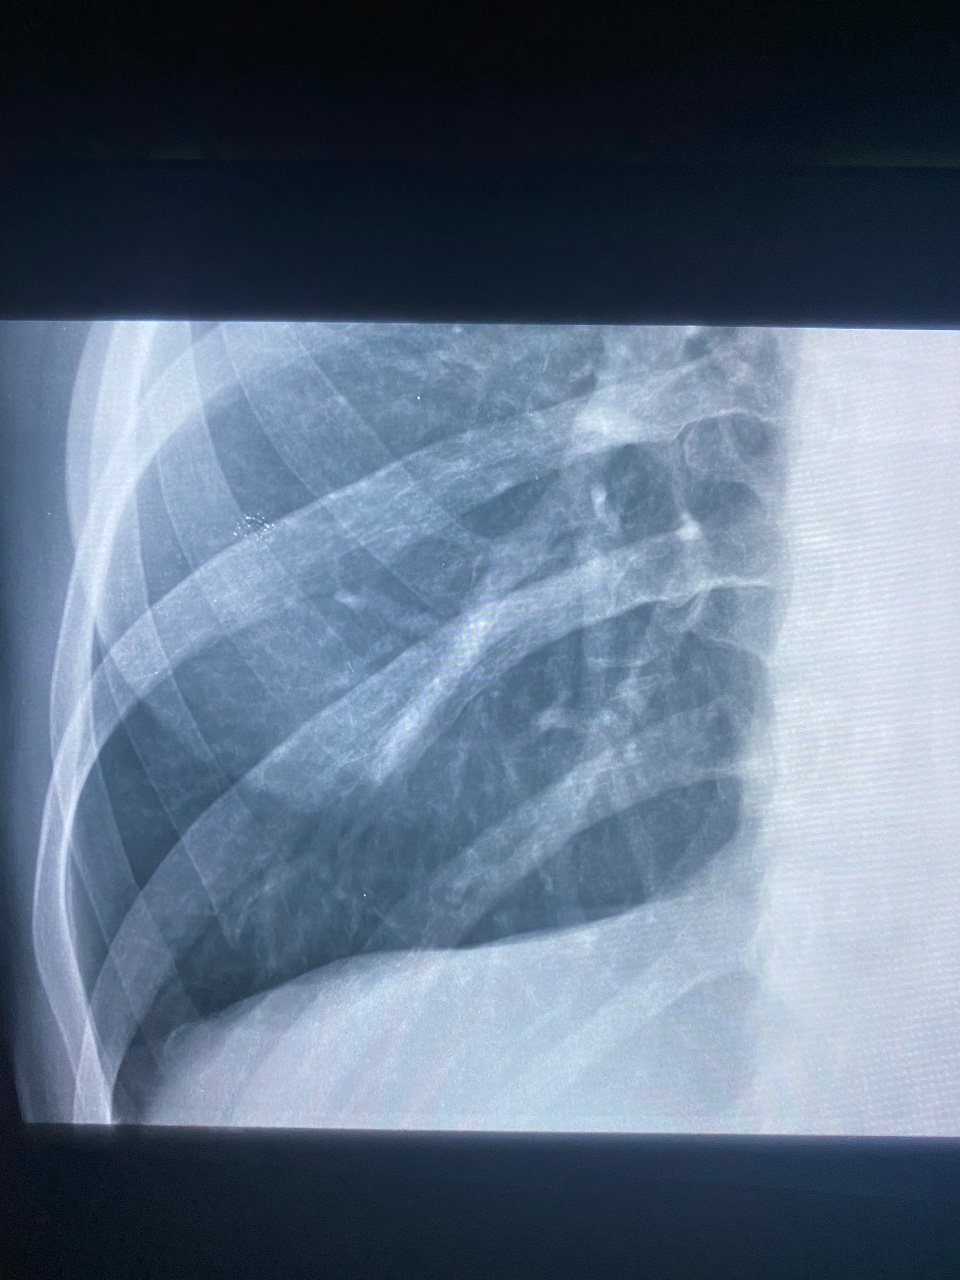

Что такое малоконтрастная рентгенограмма органов грудной клетки